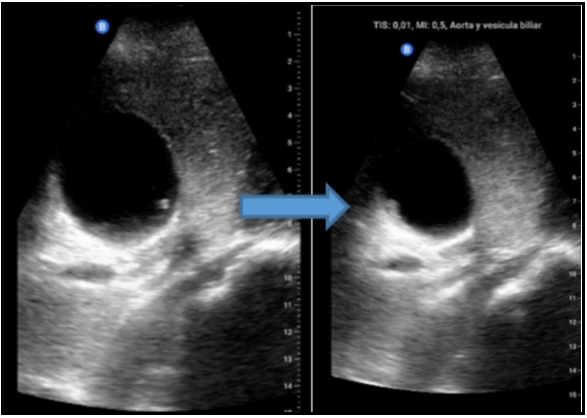

Ascariasis in the bile ducts: A case report